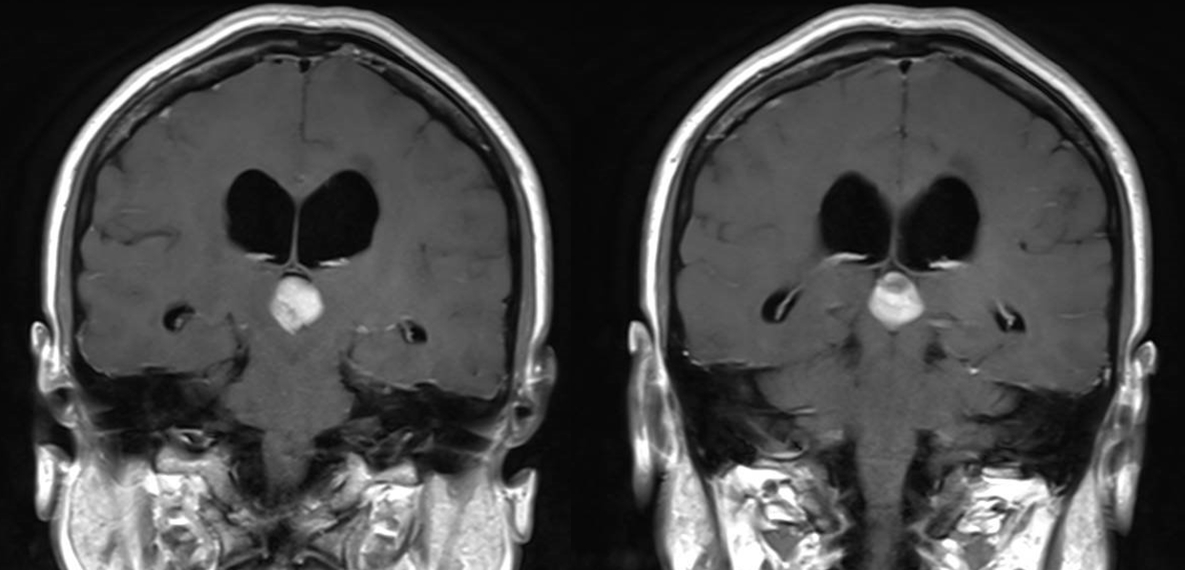

诊断:三脑室占位,梗阻性脑积水。

诊治过程:结合患者临床表现及影像学表现,初步诊断考虑为三脑室后部胶质瘤合并梗阻性脑积水可能性大,术前制定的手术方案为经胼胝体穹隆间入路三脑室后部肿瘤切除术+脑室镜辅助下三脑室底造瘘术,该手术方式既可切除肿瘤获取病理,同时可行三脑室底造瘘解决脑积水症状。术中采用冠状缝前额部弧形切口,术中沿纵裂牵开双侧大脑半球,探及胼胝体,沿中线切开胼胝体,分离双侧透明隔,暴露双侧穹隆,严格沿中线分离双侧穹隆,保护两侧穹隆的完整,避免引起术后的记忆力障碍,牵拉开双侧穹隆,进入中间帆,显露并分离双侧大脑内静脉继续向下,经脉络膜隔进入三脑室,完全显露肿瘤组织,肿瘤组织呈灰红色,血供极其丰富,与中脑黏连紧密,仔细分离,分块全切肿瘤,双侧大脑内静脉及中脑保护良好,中脑导水管通畅。肿瘤完全切除后,考虑到术后局部粘连、肿瘤复发等因素可能导致脑积水不缓解,置入脑室镜向前方探查,小心切开中间块,在双侧乳头体与漏斗隐窝之间,行三脑室底部造瘘并打开Liliequist膜及基底动脉旁蛛网膜,确认漏口通畅且与脚间池相通。患者术后恢复过程平稳,颅脑MRI提示肿瘤切除满意,脑积水缓解。术后病理结果示:中枢神经细胞瘤(2级)。术后予以放疗GTV 5400cGy、PTV 5040cGy,28f。现术后已3年,复查未见肿瘤复发,脑积水已完全缓解。